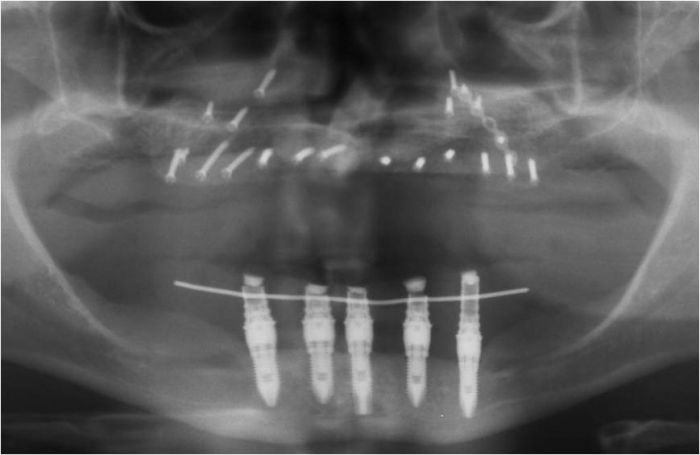

Rx do enxerto ósseo de maxila, com osso de crista ilíaca

Rx dos implantes Cone Morse superiores

Próteses fixas em resina superior e inferior sobre implantes